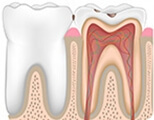

Explore how pulpitis and periapical periodontitis develop

Root canal is the best treatment for pulpitis and periapical periodontitis